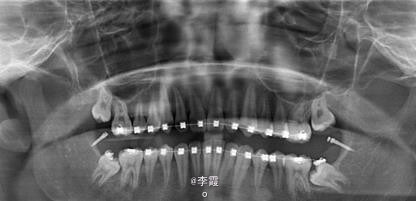

患者、马xx、15岁,主诉:牙齿不齐,要求正畸治疗。 转诊外科行下颌升支处种植体支抗直立下颌磨牙。通过患者的术前影像资料,47牙冠远中有部分骨质覆盖牙冠,采取翻瓣导萌直立磨牙。37采取电刀环切导萌直立磨牙。